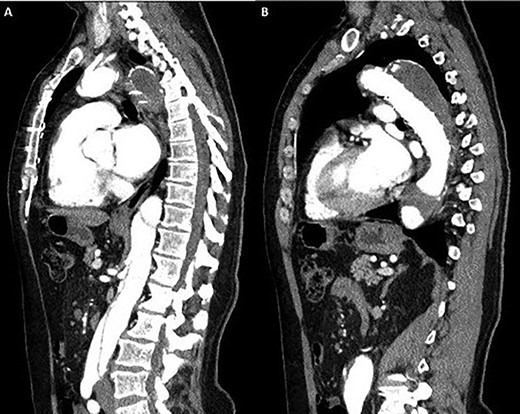

(A) Coronal section demonstrating the distal arch with the left vertebral and subclavian arteries visible; (B) coronal section demonstrating aneurysmal enlargement of the descending thoracic aorta and Type B dissection.

A 52-year-old gentleman presented to our institution with a previous history of TBAD (diagnosed 3 years previously), which was managed conservatively. His comorbidities included hypertension and excision of a left frontal cavernoma with no family history of aortic aneurysm or dissection. Following his initial presentation of chest pain, the patient had remained asymptomatic and stable. Surveillance management was initially instituted and the case discussed at the aortic multidisciplinary meeting. Due to retrograde extension of the TBAD into the distal arch, persistence of the false lumen, increasing descending aortic dimensions (6.0 cm) and an anomalous left vertebral artery originating from the aortic arch, the patient proceeded to aortic arch surgery and antegrade deployment of the stent into the descending aorta with a FET graft (Figs 1, 2). Preoperative coronary angiography and transoesophageal echocardiography revealed no coronary artery disease and a competent trileaflet aortic valve with preserved left ventricular function.